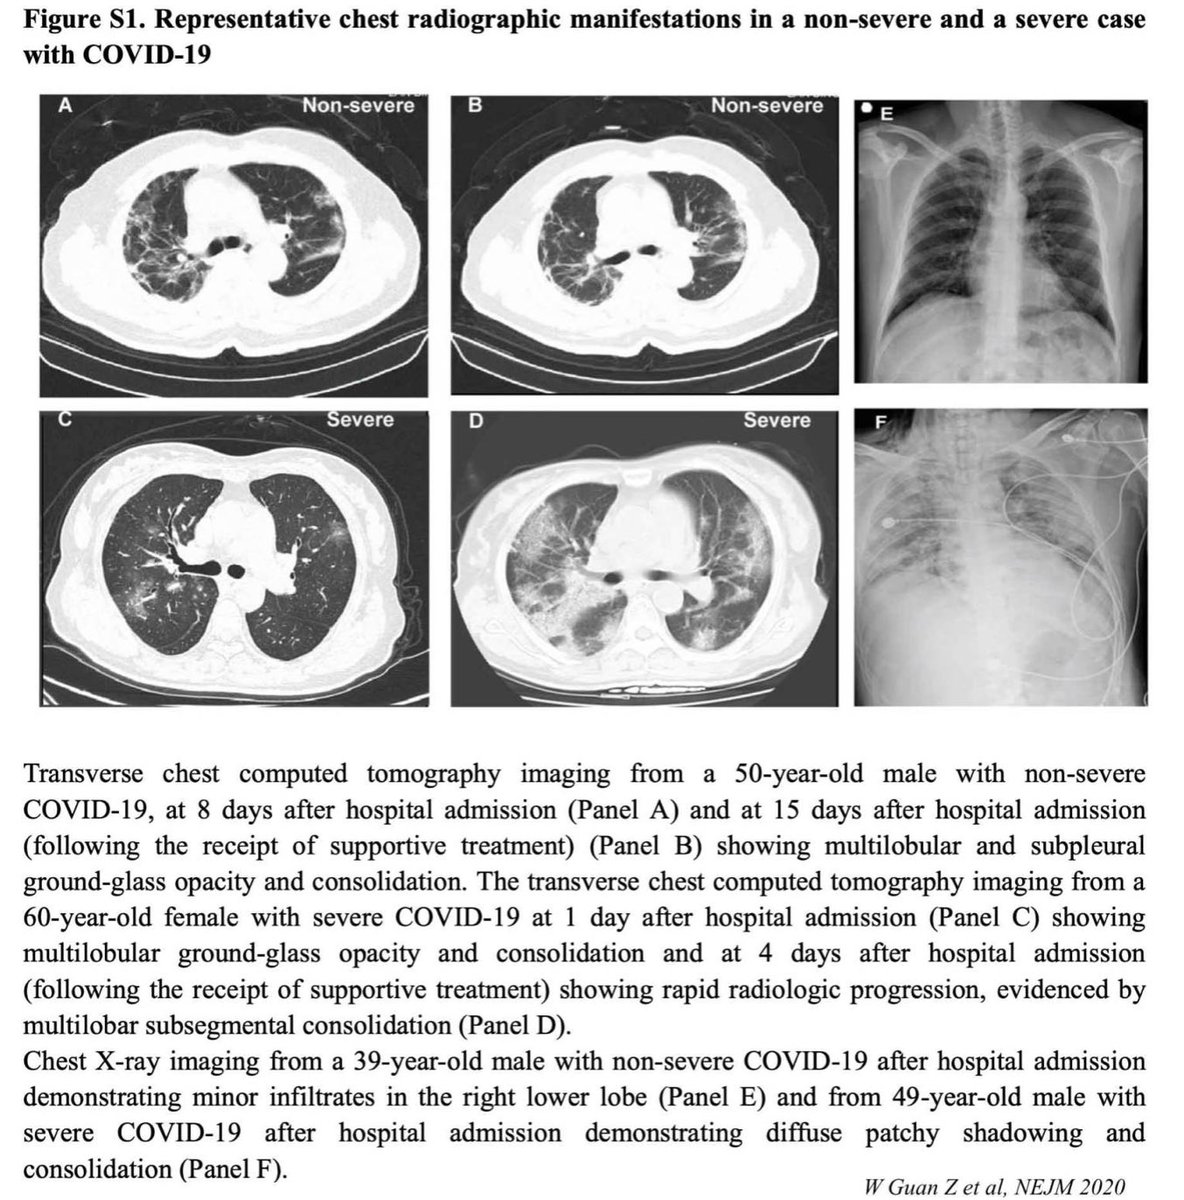

Консолидации кт

Консолидации кт 116 фотографий